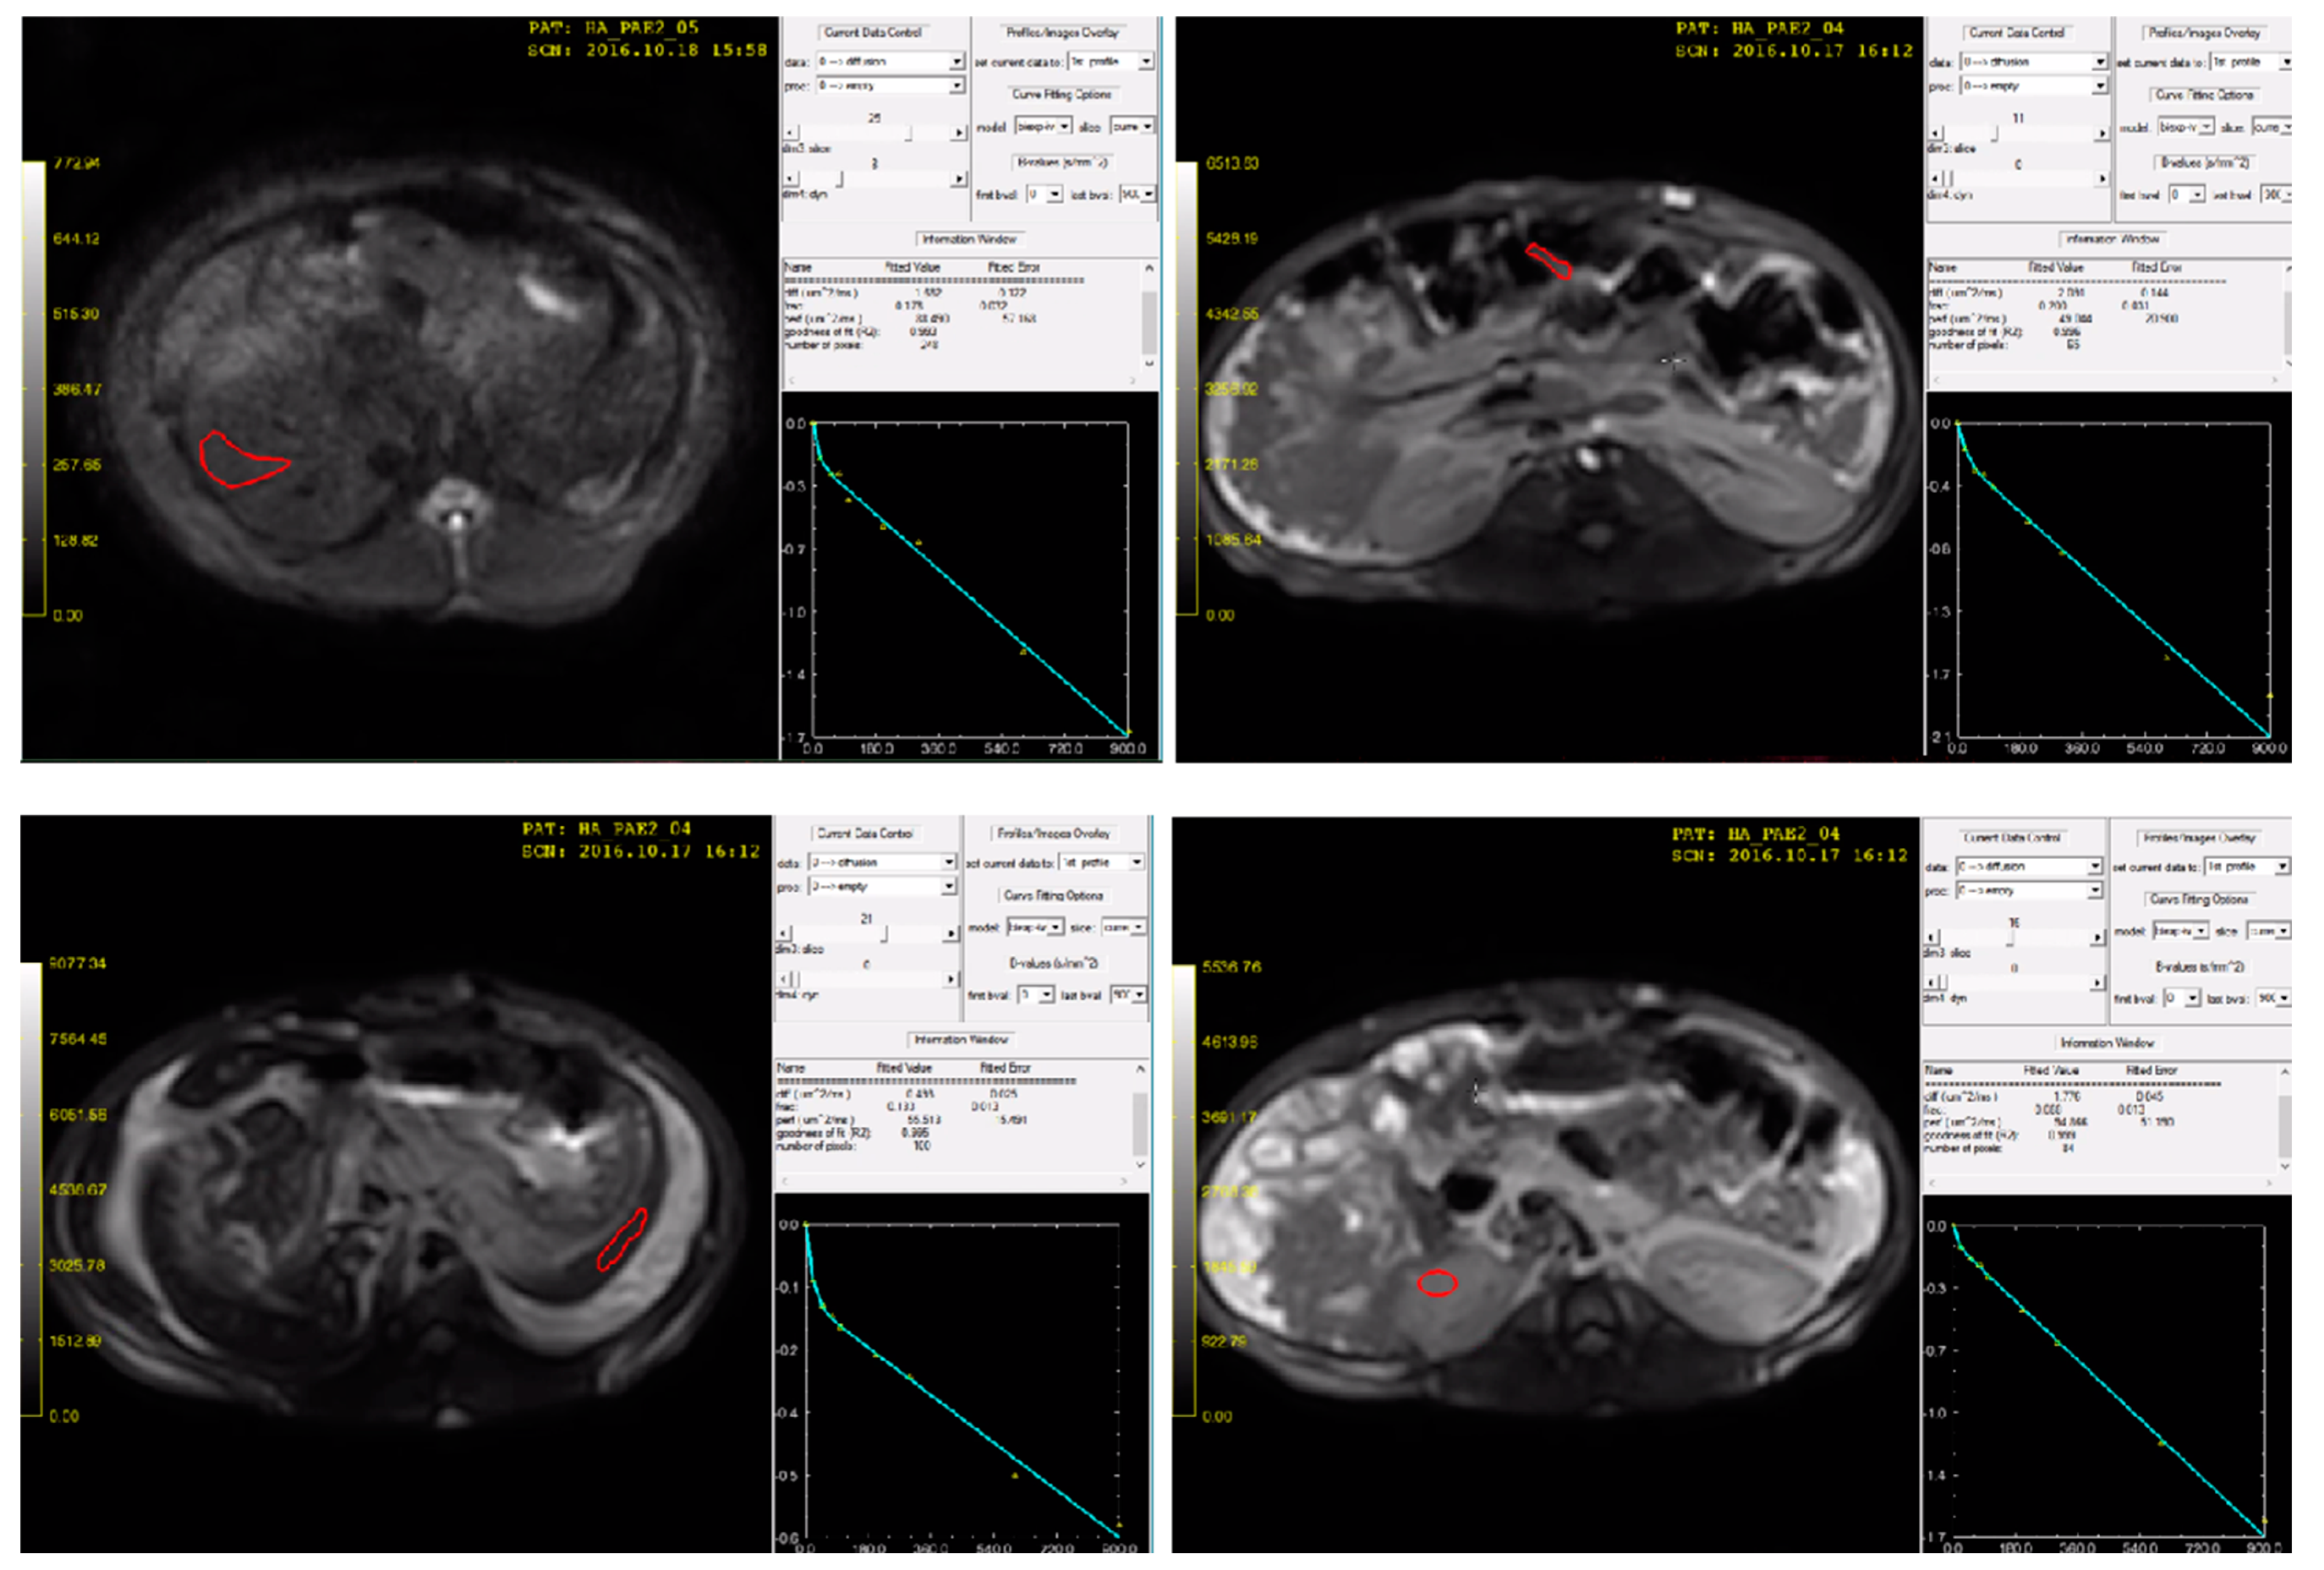

2.4.1. DW-MRI Data

2.4.2. Image Analysis